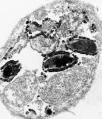

Encephalitozoon intestinalis

| Comment: | Encephalitozoon intestinalis causes gastrointestinal disease frequently associated with other clinical manifestations (nephritis) in immunocompromised HIV-infected patients. |